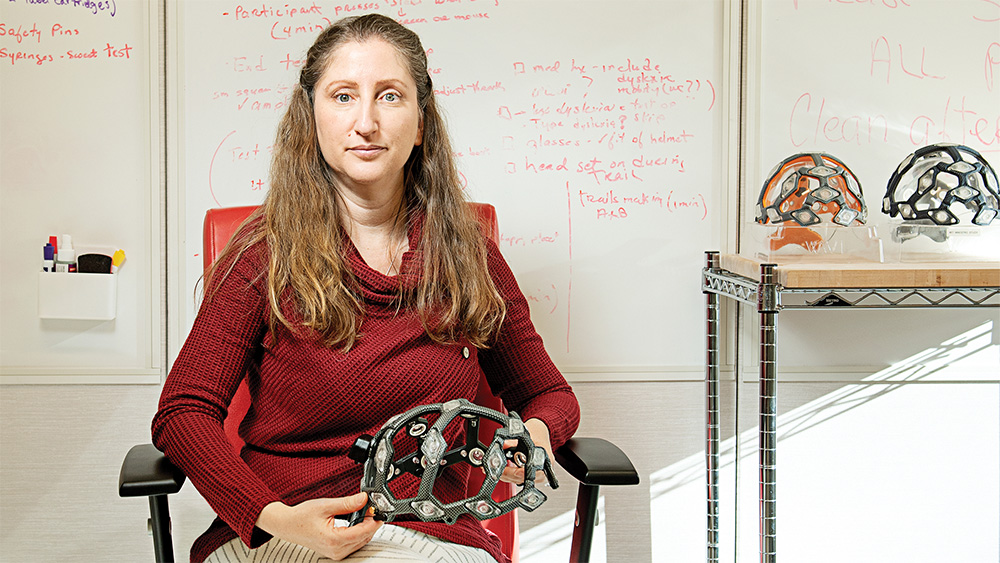

“Long Covid looks exactly, and I mean exactly, like chronic Lyme,” Michal “Mikki” Tal says. Her research group investigates why some people develop chronic illness from acute infections, and works to identify biomarkers for chronic Lyme and long Covid.